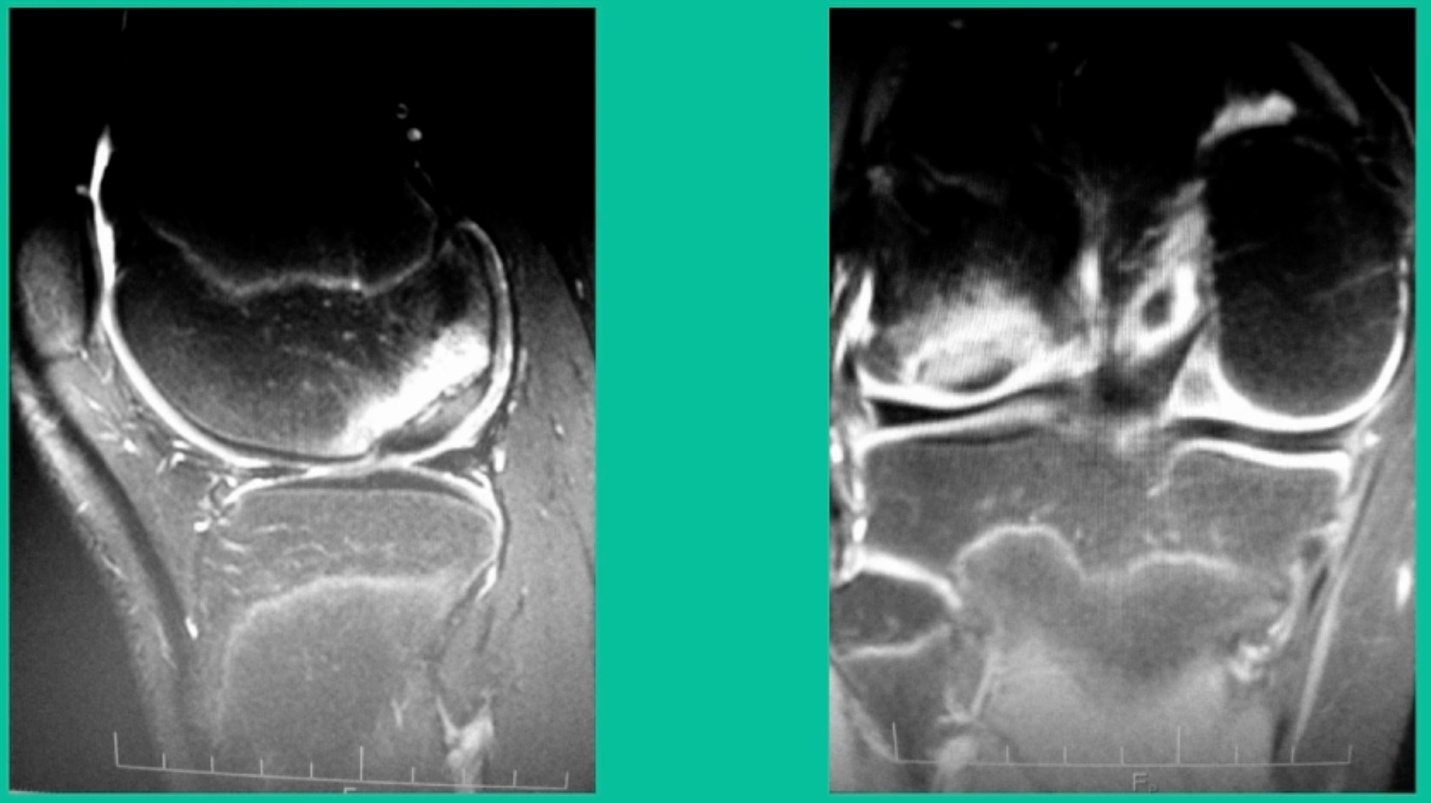

43-Year-Old, symptomatic medial femoral condyle.

D1 football player formally, affecting ADLs. For this one, I initially just wanted to watch it. This looks pretty small when he came in. Let’s see what happens. Six months later, this is where he progressed to.

We get in there, it’s delaminated, not much bone, nothing to fix in my mind, and so we drilled it.

How do these do? There’s actually reasonable data for marrow stimulation for OCD. But if you have the option for small defects, I would prefer an osteochondral allograft over microfracture based on the literature. That’s the take-home. Marrow stimulation, if you do it, you’re probably better off drilling it. We showed that we could reduce revision rates with marrow stimulation by two-thirds if you drill it versus use a microfracture awl.